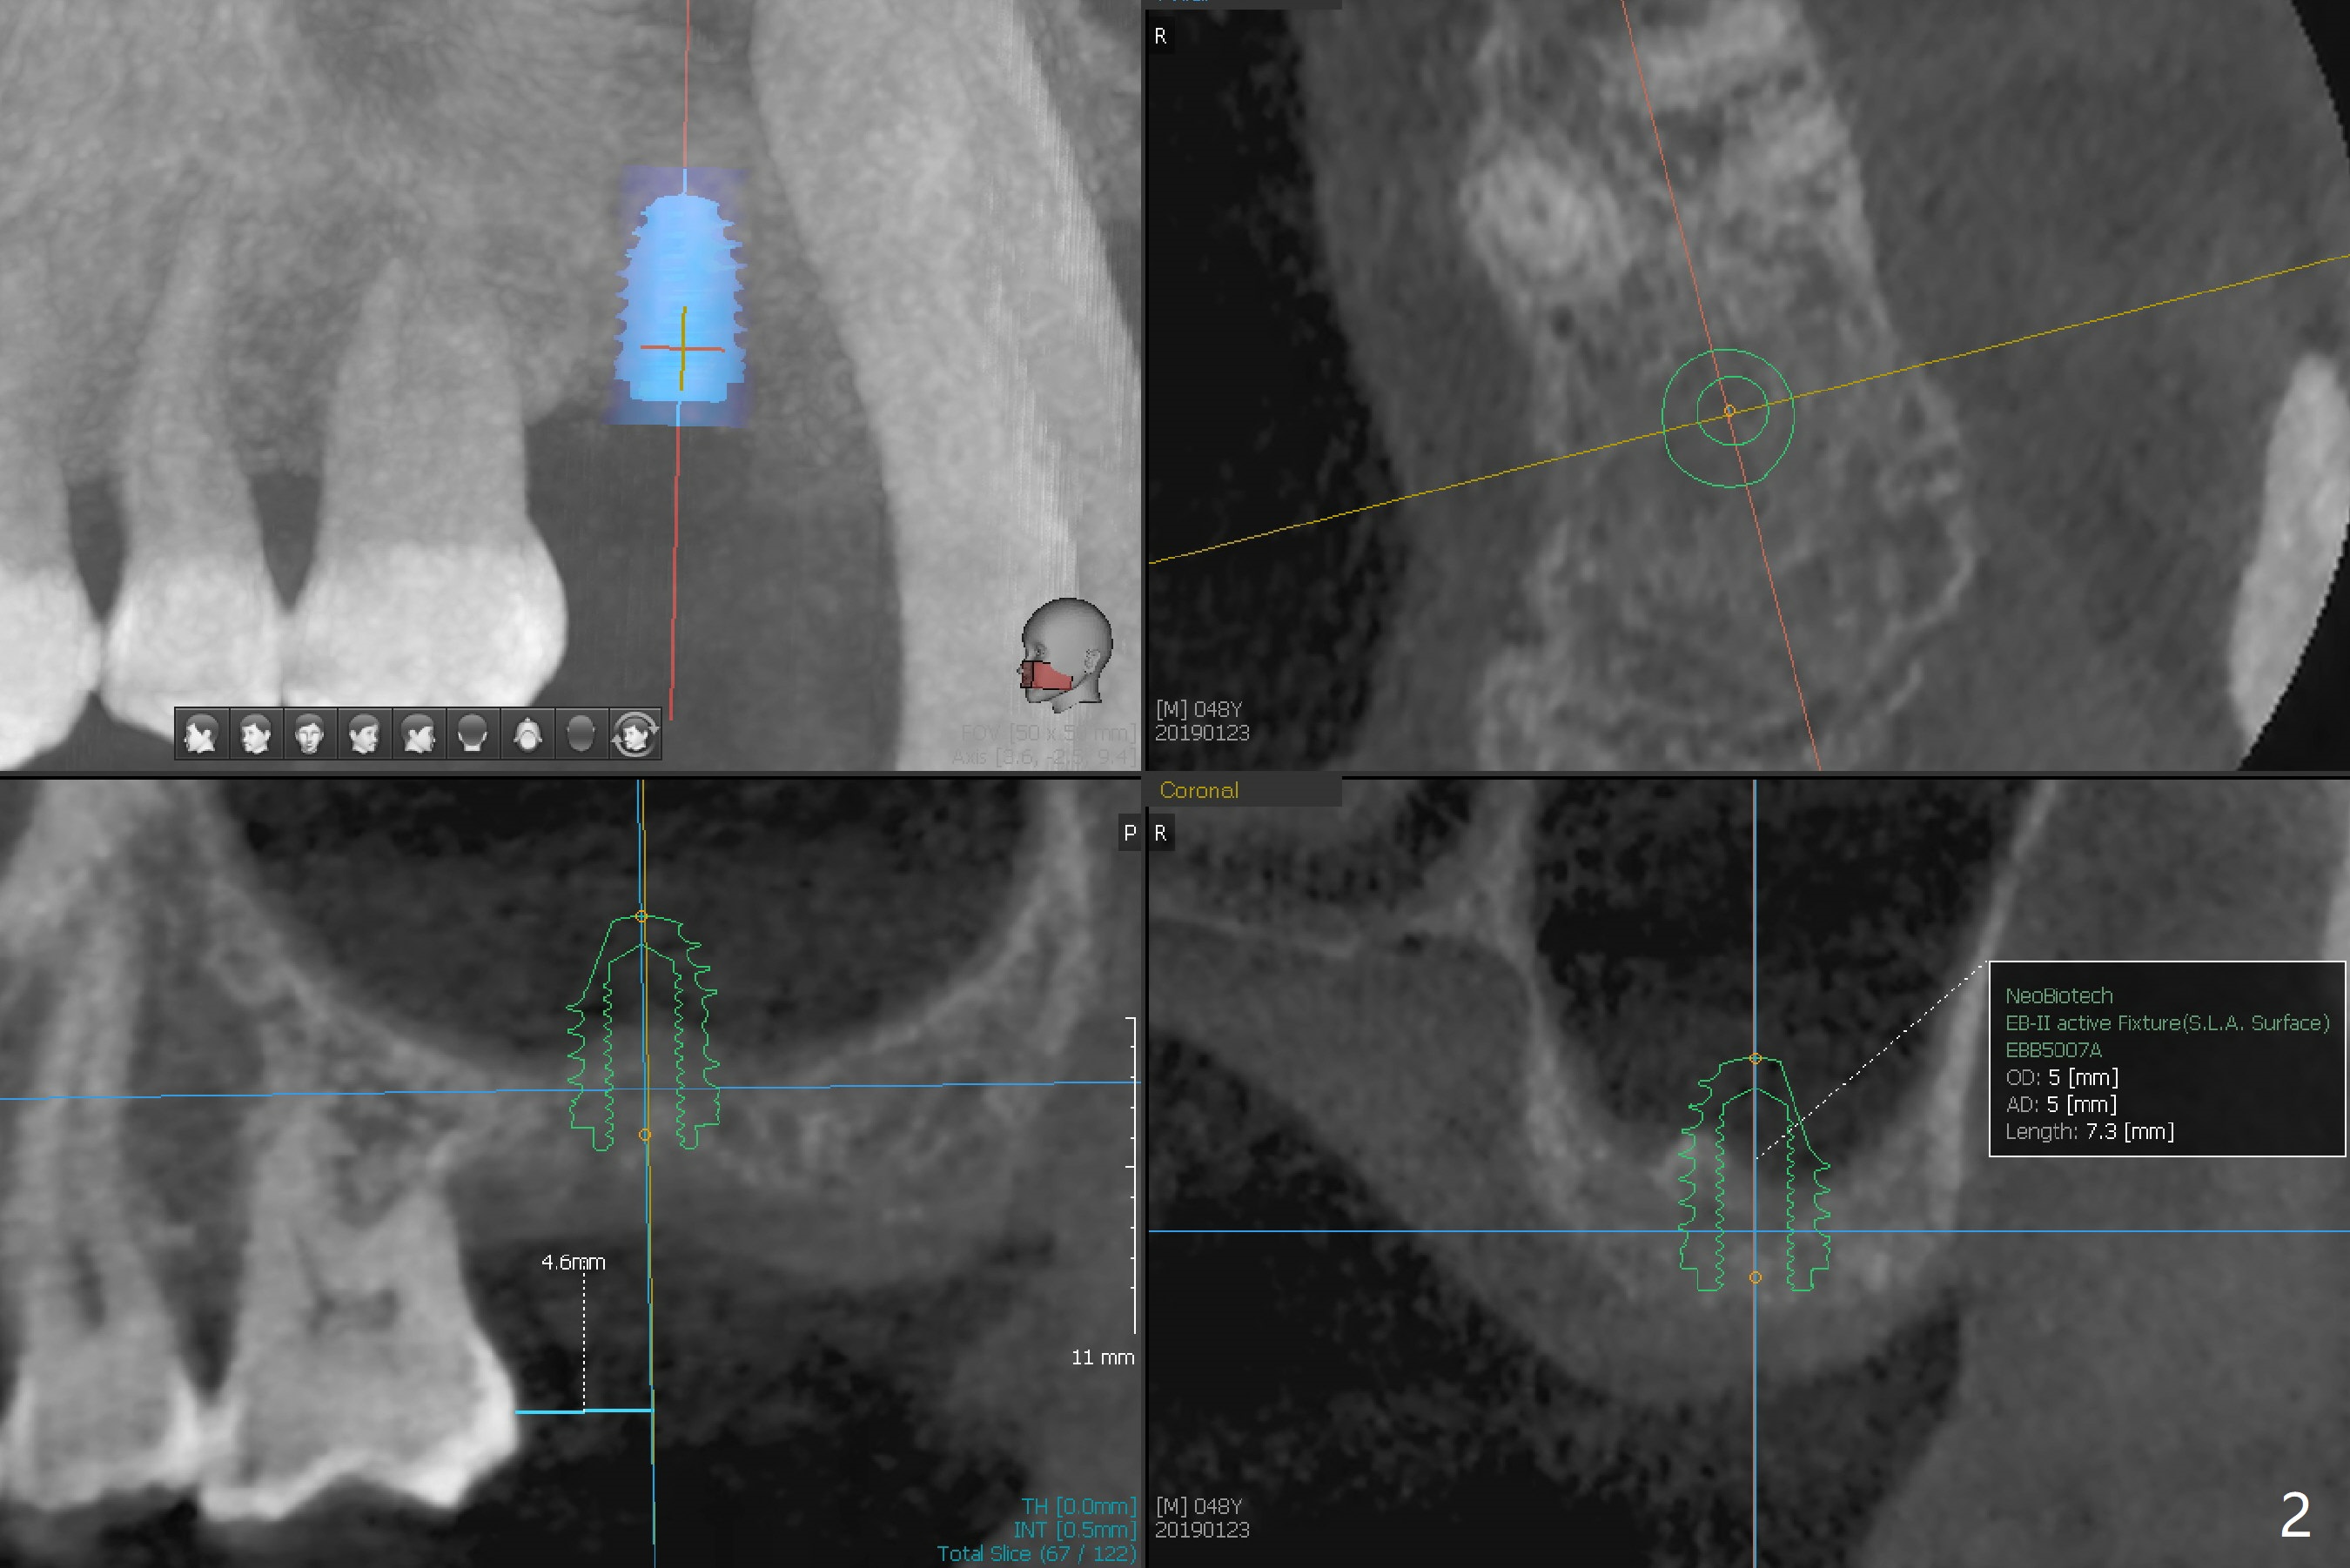

A 48-year-old man returns for CT 4.5 months post infected implant removal with bone graft at #15. The bone height reduces from 6-10 mm to ~ 4 mm (Fig.1). To place a 5x7.3 mm implant (Fig.2), initial osteotomy for ~3 mm in depth and in diameter will be aided by guided surgery (Fig.3 (red line: sinus membrane)). Internal sinus lift is going to be conducted with Magic Lifter free hand or in the middle of the tube (Fig.4 arrows). The specially designed lifter is able to lift the sinus floor without tearing the membrane. To prevent and repair membrane injury, one or 2 pieces of PRF membrane will be inserted underneath the lifted structures (Fig.5 yellow), followed by bone graft (green circles). Then 3.5-4.5 mm taps will be used with guide to further expand and condense the osteotomy. With more graft to be placed, the 5x7.3 mm implant will be placed (Fig.6 pink).